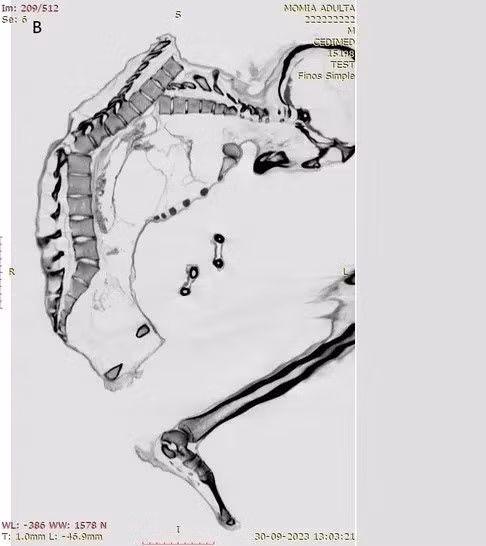

Kết quả kiểm tra xác ướp tìm thấy gần một mỏ ngọc lam ở sa mạc Atacama cho thấy người đàn ông này là một thợ mỏ tử vong trong vụ tai nạn lao động thương tâm.